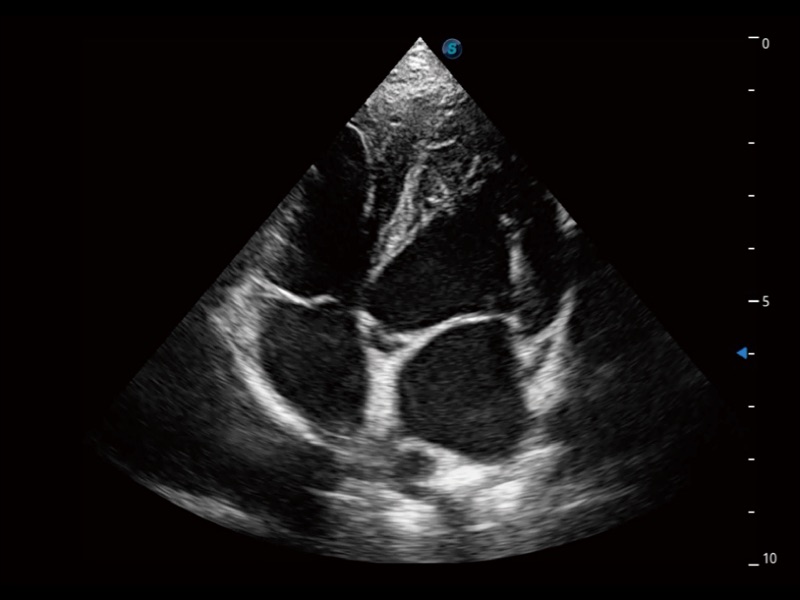

ProPet 70 进一步提升了微米成像算法,更加注重对基础原始图像的还原和保留,在有效减少斑点噪声、增强组织边界显示的同时,避免过度优化丟失真实的解剖信息。

ProPet 70专为动物医生设计,对不同的动物体型和生理结构作出了针对性的优化。通过动物影像专用软件,可满足个性化的应用需求,帮助动物医生获得更精确的诊断数据。

ProPet 70 全新的动物超声智能软件和丰富的探头群,为动物医生提供了高清晰度和精细分辨率的图像,无论在宠物、马科、畜牧还是实验室动物等应用中都可以轻松应对,为您的日常工作带来满意的体验。